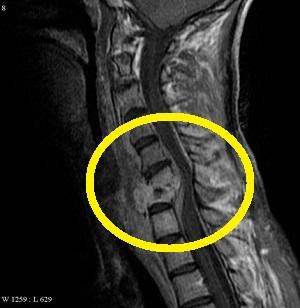

Наиболее часто эпидурит диагностируется у людей с межпозвоночной грыжей и спондилезом. Эти пациенты находятся в группе риска и должны внимательно ознакомиться с клинической картиной заболевания. Как выглядит эпидурит – смотрите на фото.

После подтверждения диагноза эпидурита позвоночника с помощью томографического исследования и определения локализации поражения, врач назначает соответствующее лечение.